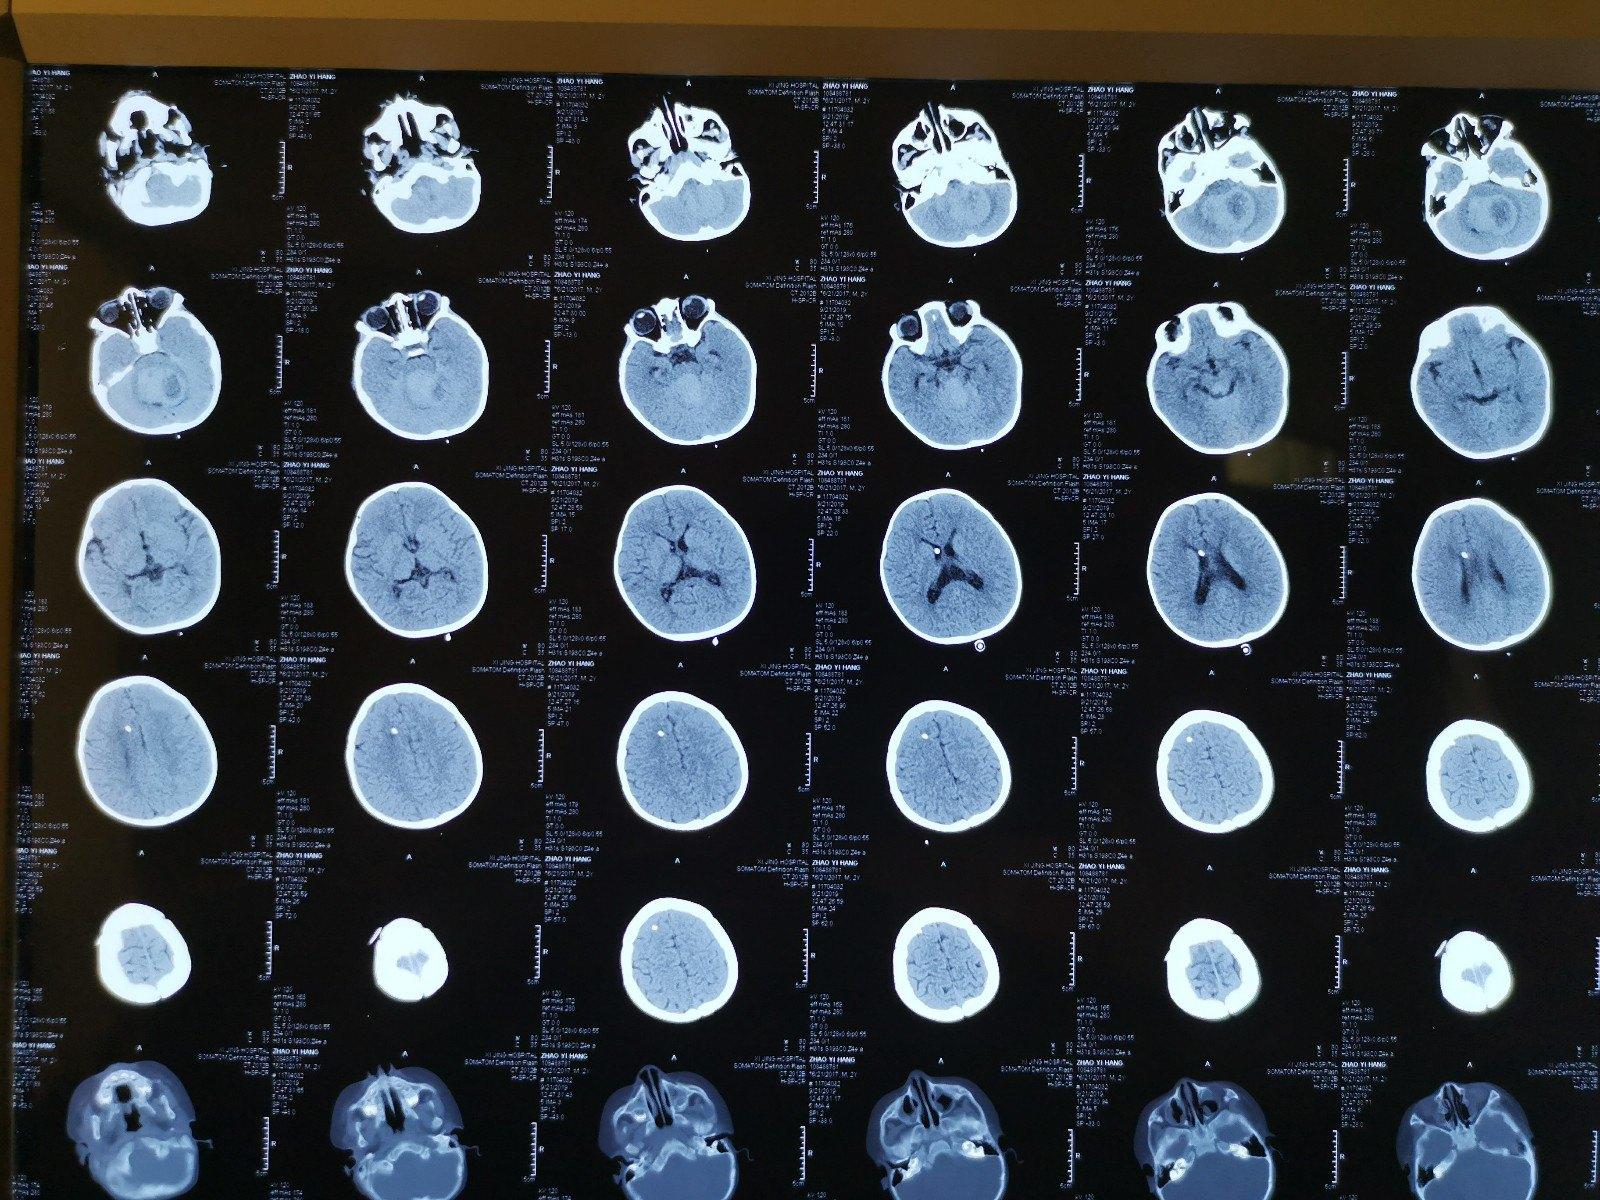

儿童脑瘤

宫剑教授病例分享十六儿童型脑膜瘤的外科治疗

始终如一提高小儿脑瘤的治愈率儿童颅内巨大肿瘤手术一例